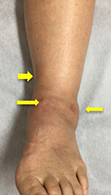

歩行時に軟骨のすり減っている部分に疼痛が生じます。病態が進行すると、外観上も足の変形が認められます。

単純レントゲン写真

(矢印)